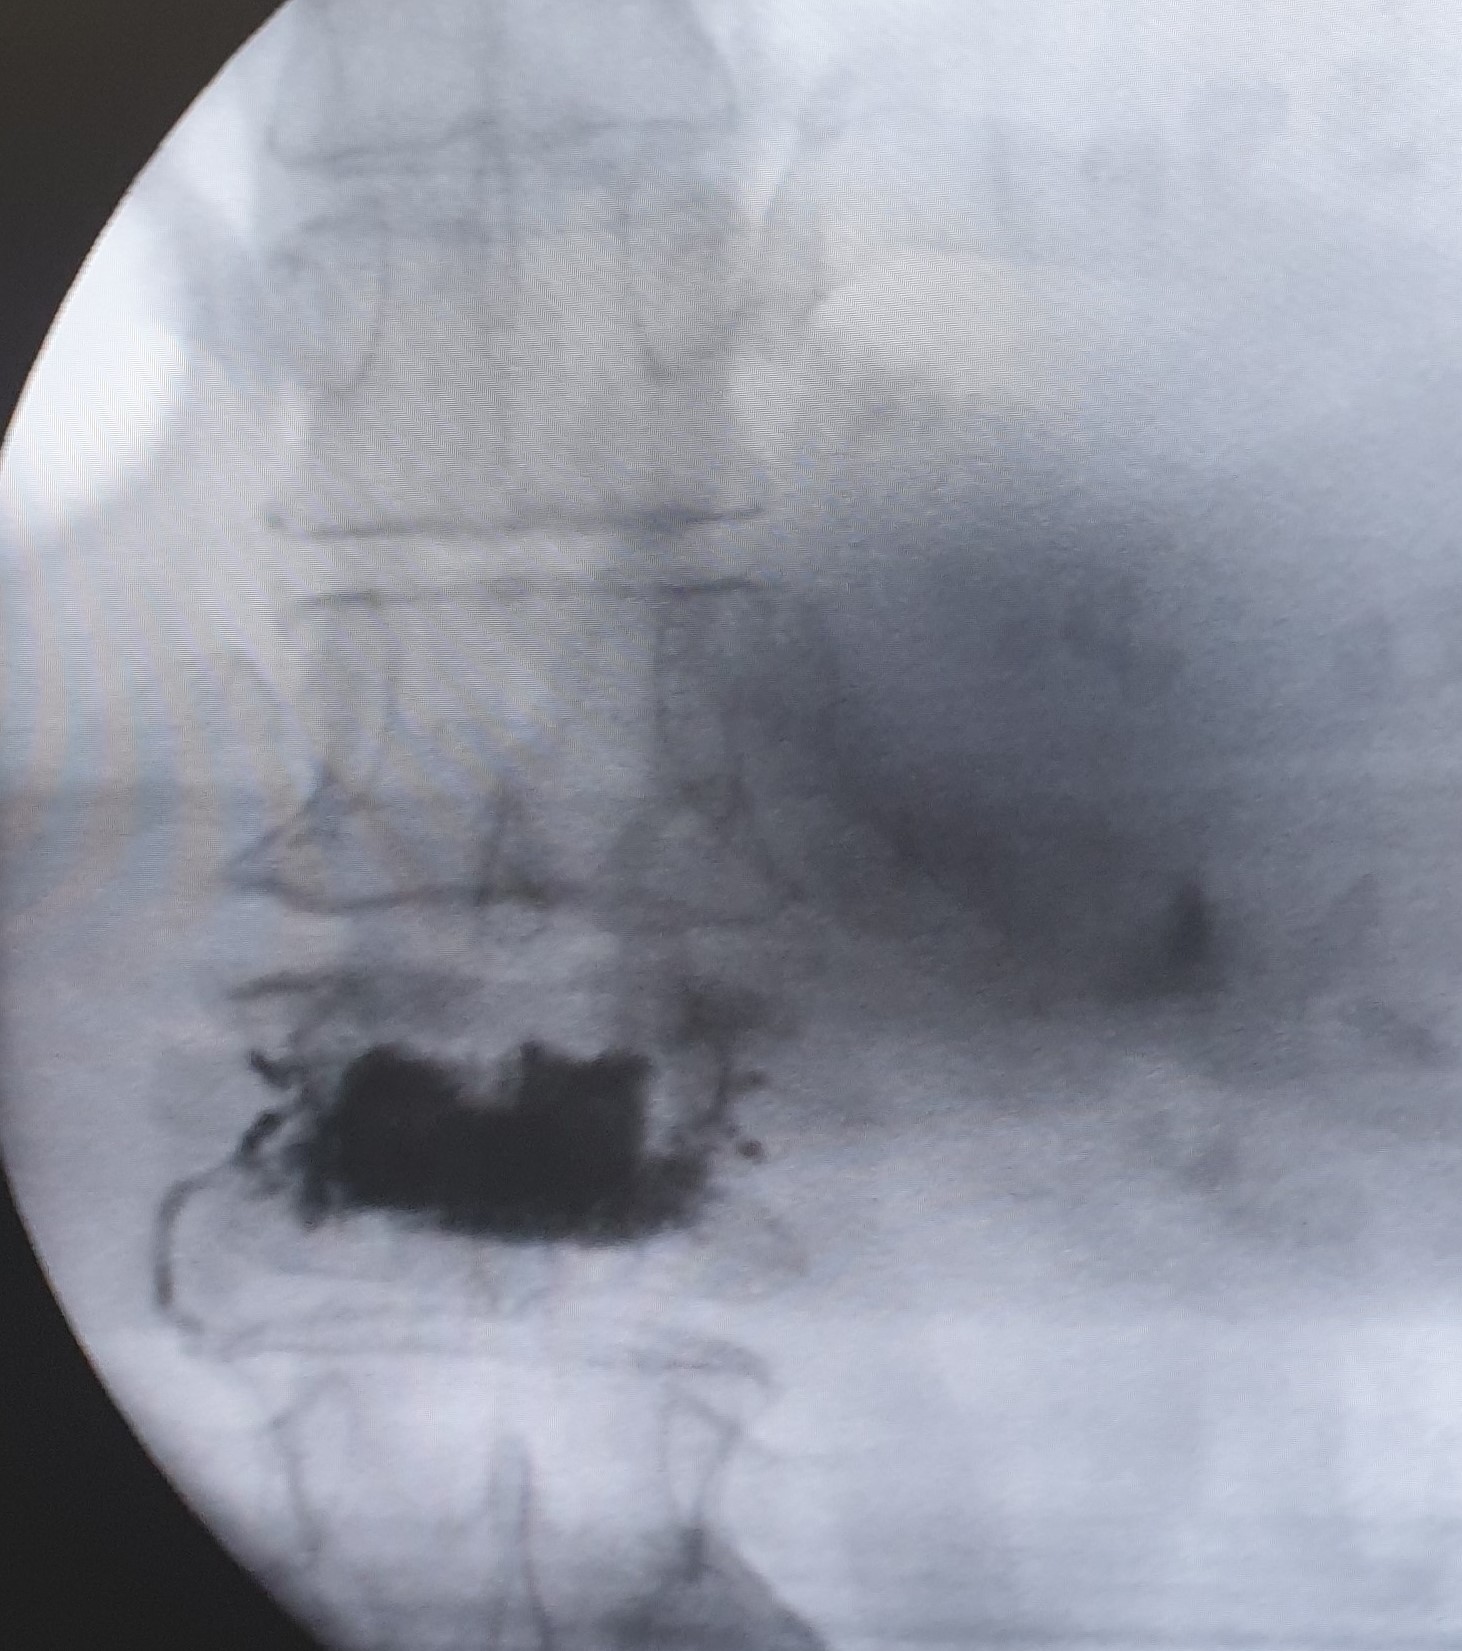

Η κυφοπλαστική και η σπονδυλοπλαστική αποτελούν ελάχιστα επεμβατικές τεχνικές αντιμετώπισης του πόνου που προκαλείται από συμπιεστικά καταγμάτα των σπονδύλων, επί εδάφους οστεοπόρωσης ή μεταστατικής νόσου. H προσπέλαση και στις δύο περιπτώσεις γίνεται διαδερμικά και κάτω από συνεχή ακτινοσκοπική καθοδήγηση.

Η κυφοπλαστική αποκαθιστά το ύψος του σπονδύλου, με χρήση ειδικού μπαλονιού και εισαγωγή τσιμέντου, ενώ η σπονδυλοπλαστική αφορά σε απλή εισαγωγή τσιμέντου στον καταγματικό σπόνδυλο. Και οι δύο τεχνικές γίνονται μέσω ειδικών βελόνων-trocar που εισάγονται διαδερμικά υπό ακτινοσκοπικό έλεγχο, στους αυχένες των σπονδύλων και προωθούνται στο σπονδυλικό σώμα, όπου γίνεται η έγχυση του τσιμέντου ταχείας πήξης. Το τσιμέντο σταθεροποιεί τον σπόνδυλο και αποτρέπει την ανάπτυξη κύφωσης στα πάσχοντα σημεία.

Η κυφοπλαστική επιλέγεται για πρόσφατα κατάγματα (έως 6 μηνών). Και οι δύο τεχνικές μπορούν να εφαρμοσθούν σε πολλαπλά επίπεδα της σπονδυλικής στήλης.